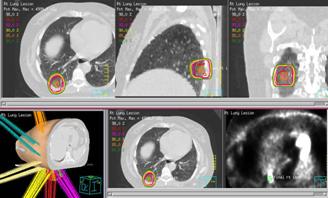

Photo: A radiation treatment plan for extra-cranial lung stereotactic radiotherapy.

Stereotactic body radiation therapy (SBRT)

Stereotactic body radiation therapy is a type of external radiation given in fewer sessions with a higher dosage of targeted radiation. It will require longer treatment times which are typically done in 3-5 treatments over the course of 1-2 weeks.